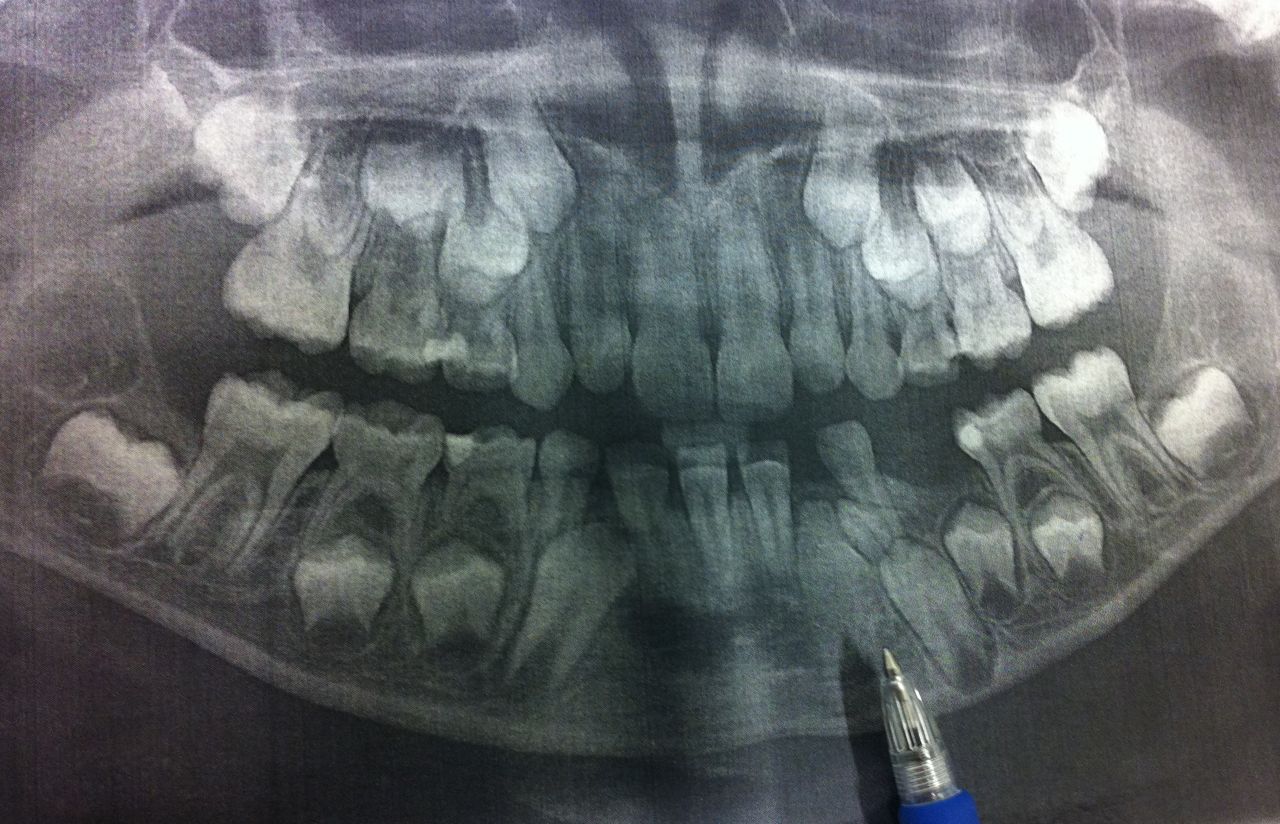

医生把三三牙齿的照片在电脑上放出来给我们看,说,这里,有一颗多余的牙,已经长出来的,旁边牙床还有一颗多余的牙,还没长出来。这两颗牙都得拔掉,否则就会阻挡成年牙长出来。

我完全看不懂X光照片,只觉得那些牙齿的影子乱七八糟地堆叠着。医生介绍的情况,我们也 非常认同。所以医生就和我们说了她的计划。要拔掉那两颗多余的牙,就必须也拔掉那两颗门牙。现在正好也该是三三换门牙的年纪。三三年纪小,估计手术时很难保持安静,所以最好用全麻。我们也同意了。然后填了一份资料,里面是三三的各项生理指标,安排手术的时候要考虑的。